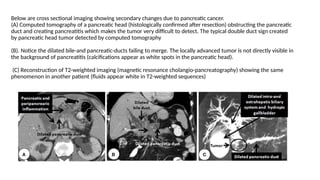

Below are cross sectional imaging showing secondary changes due to pancreatic cancer.

(A) Computed tomography of a pancreatic head (histologically confirmed after resection) obstructing the pancreatic

duct and creating pancreatitis which makes the tumor very difficult to detect. The typical double duct sign created

by pancreatic head tumor detected by computed tomography

(B). Notice the dilated bile-and pancreatic-ducts failing to merge. The locally advanced tumor is not directly visible in

the background of pancreatitis (calcifications appear as white spots in the pancreatic head).

(C) Reconstruction of T2-weighted imaging (magnetic resonance cholangio-pancreatography) showing the same

phenomenon in another patient (fluids appear white in T2-weighted sequences)